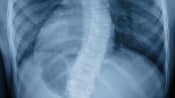

Posterior view of the adolescent spine showing thoracic scoliosis.